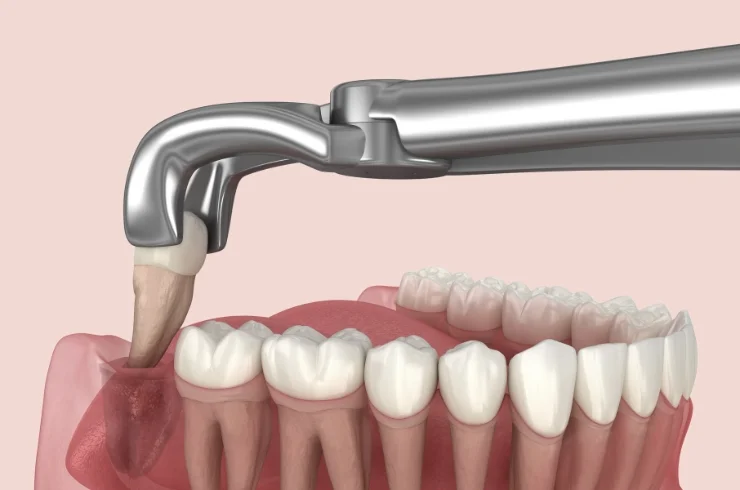

Wisdom Tooth Extraction

Wisdom tooth extraction removes impacted or problematic wisdom teeth to prevent pain, infection, and damage to adjacent teeth, promoting better oral health and alignment.